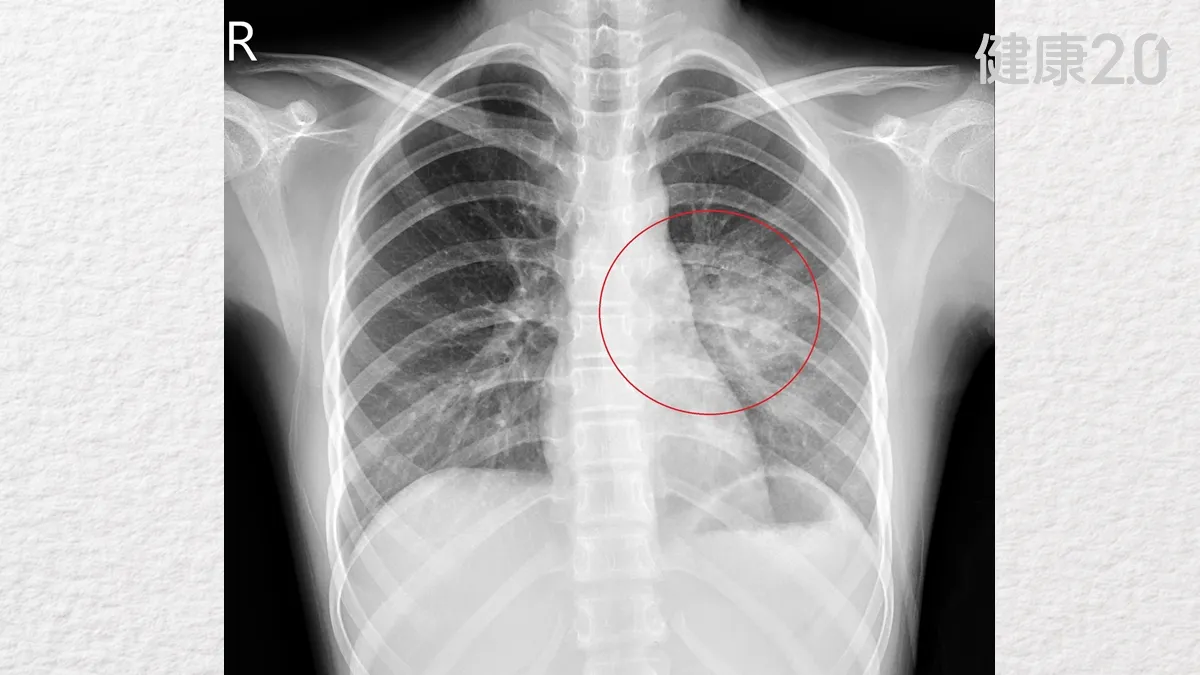

這類肺部結構異常大多能在懷孕中期透過例行檢查發現,但也有部分病灶體積較小、症狀不明顯,直到孩童長大後,因其他疾病接受胸部影像檢查時才被意外發現。像這名女童就是因為住院期間安排X光檢查,兒科主任陳傑賀看報告時察覺有異,經討論並反覆確認,才證實是CPAM肺部囊腫。

劉柏毅提醒,CPAM的臨床表現與病灶大小、位置有關,且根據囊腫大小及組織型態也有不同嚴重度分類。部分病童出生後呼吸順暢、沒有明顯異狀,直到因其他感染或不明原因咳嗽、喘鳴,就醫拍攝X光或電腦斷層時,才赫然發現肺部異常結構。也有部分新生兒在出生後即出現呼吸窘迫、臉色發白、哺乳困難等現象,需立即插管治療。